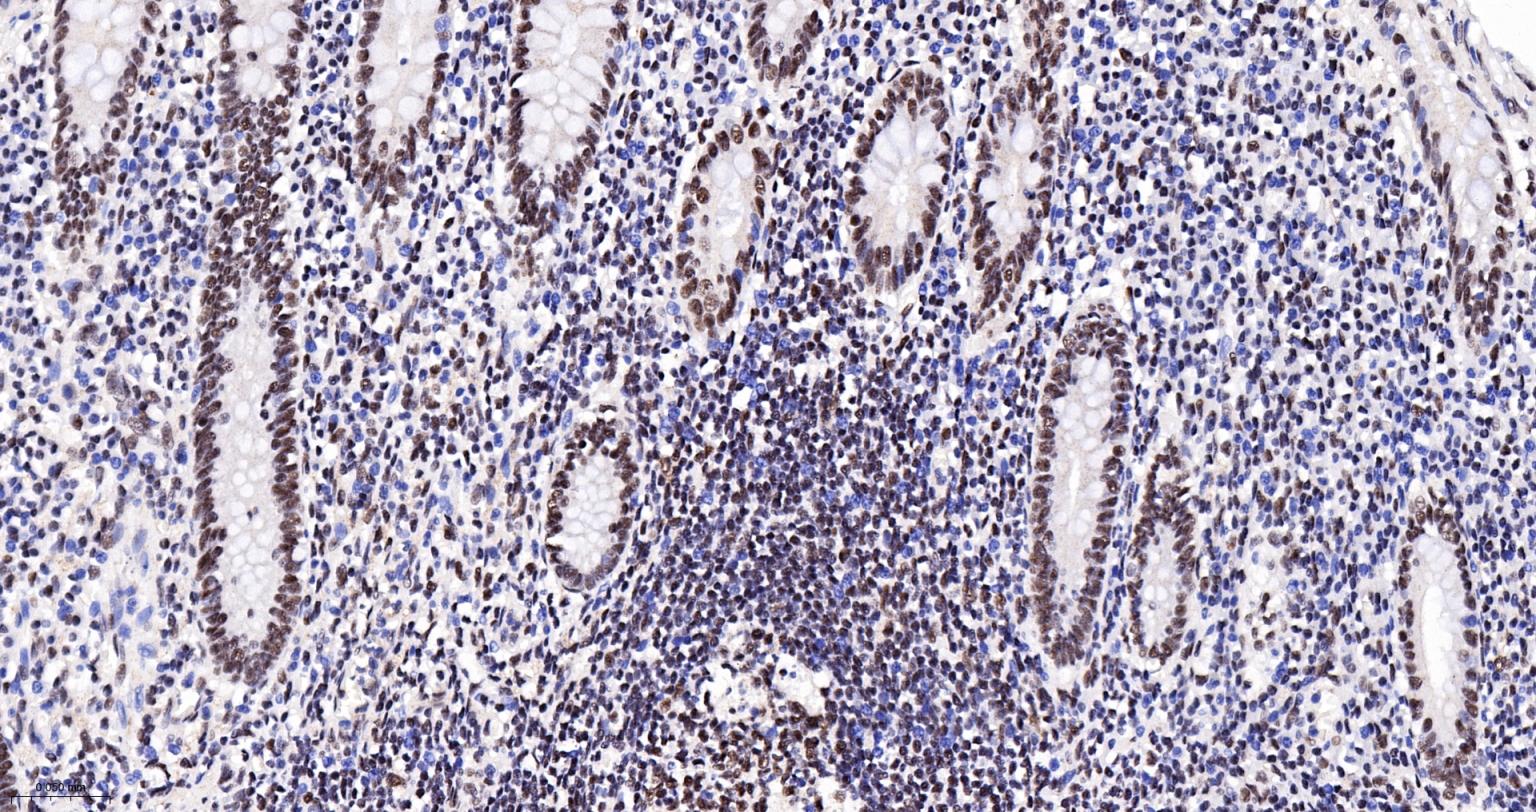

Paraformaldehyde-fixed, paraffin embedded Human appendix; Antigen retrieval by boiling in sodium citrate buffer (pH6.0) for 15 min; The section was incubated with CDC5L Monoclonal Antibody, Unconjugated (bsm-61335R) at 1:200 overnight at 4°C, followed by conjugation to the bs-0295G-HRP and DAB (C-0010) staining.